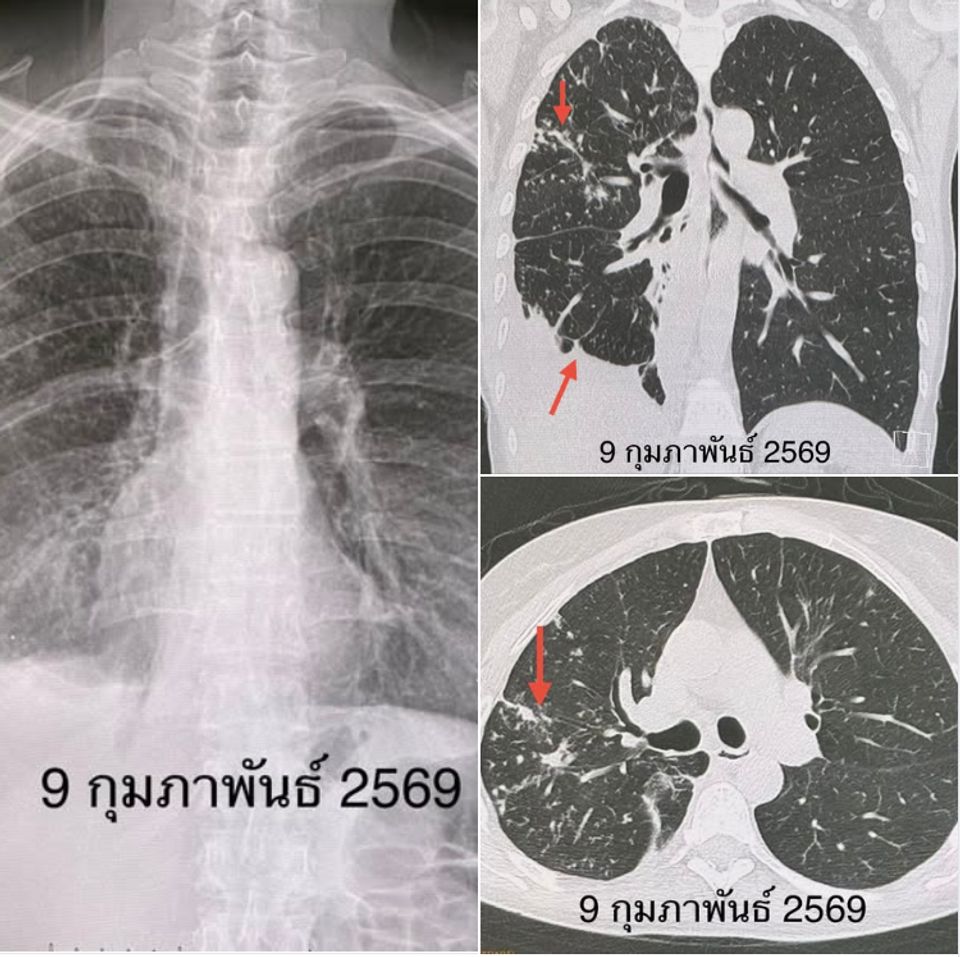

เอกซเรย์ปอด มีฝ้ากระจายในปอดข้างขวา มีน้ำเล็กน้อยในช่องเยื่อหุ้มปอดข้างขวา ทำเอกซเรย์คอมพิวเตอร์ปอด เห็นจุดกระจายในปอดข้างขวา หลอดลมโป่งพองในปอดข้างขวากลีบกลาง เห็นน้ำเล็กน้อยในเยื่อหุ้มปอดข้างขวา เนื่องจากผู้ป่วยขากเสมหะไม่ออก จึงส่องกล้องเข้าไปในหลอดลม เห็นเสมหะสีน้ำตาลในหลอดลมของปอดข้างขวา ย้อมเสมหะพบเชื้อ AFB ส่งตรวจสารพันธุกรรมพบเชื้อวัณโรค เพาะเชื้อขึ้นเชื้อวัณโรค กำลังรอผลตรวจความไวของเชื้อวัณโรคต่อยา